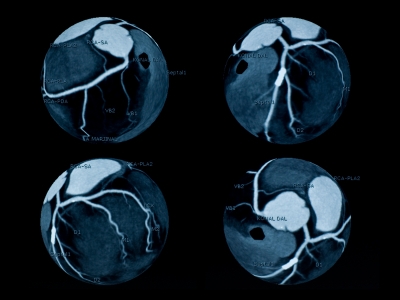

Диагноз ишемической болезни сердца является основанием для оценки состояния коронарных артерий с помощью коронарной ангиографии (коронарографии). Специальным образом выполненные рентгеновские снимки позволяют определить точное местоположение атеросклеротических бляшек и степень сужения коронарных артерий.